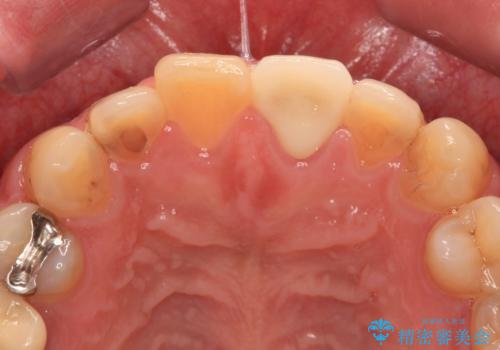

むし歯で神経が取り除かれており、歯の変色と充填材の変色などにより、つぎはぎのような前歯となっていました。

膿の出口も認められたため、まずは根管治療を実施し、オールセラミッククラウンにて補綴治療を行うこととしました。